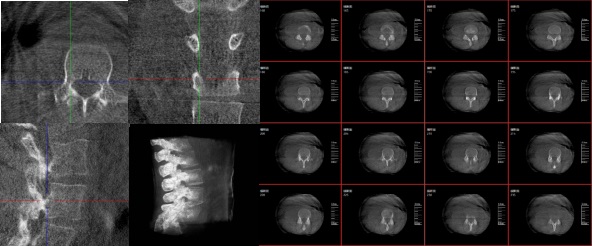

三維重建技術在醫學影像診斷領域十分重要,它是一種利用計算機軟件將二維醫學影像(如X光、CT、MRI等)轉化為三維立體圖像的技術,可以為醫生提供更直觀、更清晰的圖像信息,方便醫生從多個角度觀察病灶,從而更全面地了解病情,有助于提高診斷的準確性和效率。

6.可視化:將生成的三維模型以可視化的方式展示給醫生,幫助他們更好地理解患者的病情。

1.診斷疾病:通過三維重建技術,醫生可以更直觀、清晰地觀察到患者體內的異常情況,如腫瘤、骨折等,從而更準確地診斷疾病。

2.手術規劃:在手術前,醫生可以通過三維重建技術對患者的病變部位進行詳細的觀察和分析,制定出最佳的手術方案。

3.手術導航:在手術過程中,醫生可以通過三維重建技術實時觀察手術器械的位置,提高手術的精確性和安全性。例如在關節外科手術中,存在植入物的錯位在術中不易發現的情況,如果在術后CT中檢查出,就不可避免地需要翻修手術,這就會增加并發癥的概率以及感染風險。而通過術中三維影像設備PLX C7600的檢查,可以立即發現植入物的錯位,減少不必要的第二次手術。